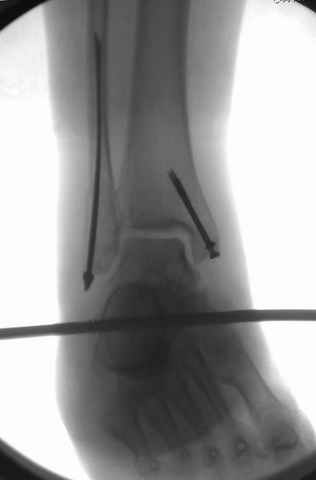

Техника сегодня более щадящая, временные несложные аппараты наружной фиксации: Spanning 2 pin ExFix, Traveling traction для лигаментотаксиса, иначе сокращенные мягкие ткани невозможно восстановить позже.

За последнее 10-12 лет после стабилизации малоберцовой кости, стали применять более усовершенный, сложный, хорошо вам известный метод

Илизарова (кстати наряду с тибиал плато, пилон является одним из показанием по применению аппарата Илизарова при травмах) или Hybrid

Fixator, из минимальных доступов комбинированный метод для восстановления суставной поверхности-фиксация каннулированными

шурупами, создания жесткой системы фиксации до сращения перелома, защита от вальгусной деформации и на место образовавщегося метафизарного дефекта- костная пластика ауто костью или его

синтетические заменители, это сегодняшная тактика лечения.